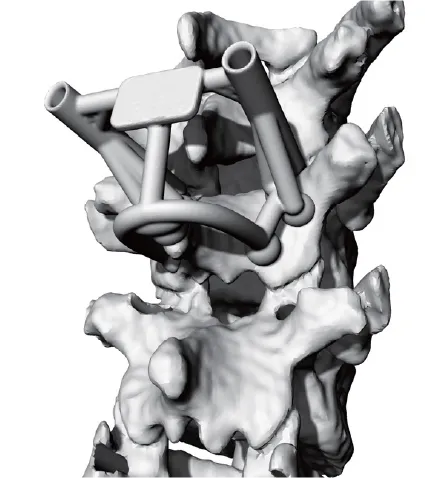

Integral G3dX

2022年に薬事承認を取得した腰椎後方固定用の人工骨です。3Dプリンターを用いて製造しています。